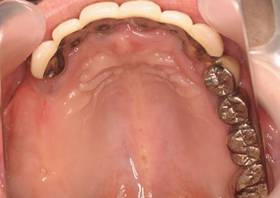

上顎

術後。上部構造はハイブリッドレジンです。しっかり嚙めるようになり喜んでいただきました。

上部構造装着後6年。ハイブリッドレジンを使用したため、少し艶がなくなってきました。上部構造の材料には金属、ハイブリッドレジン、セラミックなどがあります。セラミックはきれいですが欠けやすいため、最近はフルジルコニアを使っています。

上顎 少しすり減ってきました。